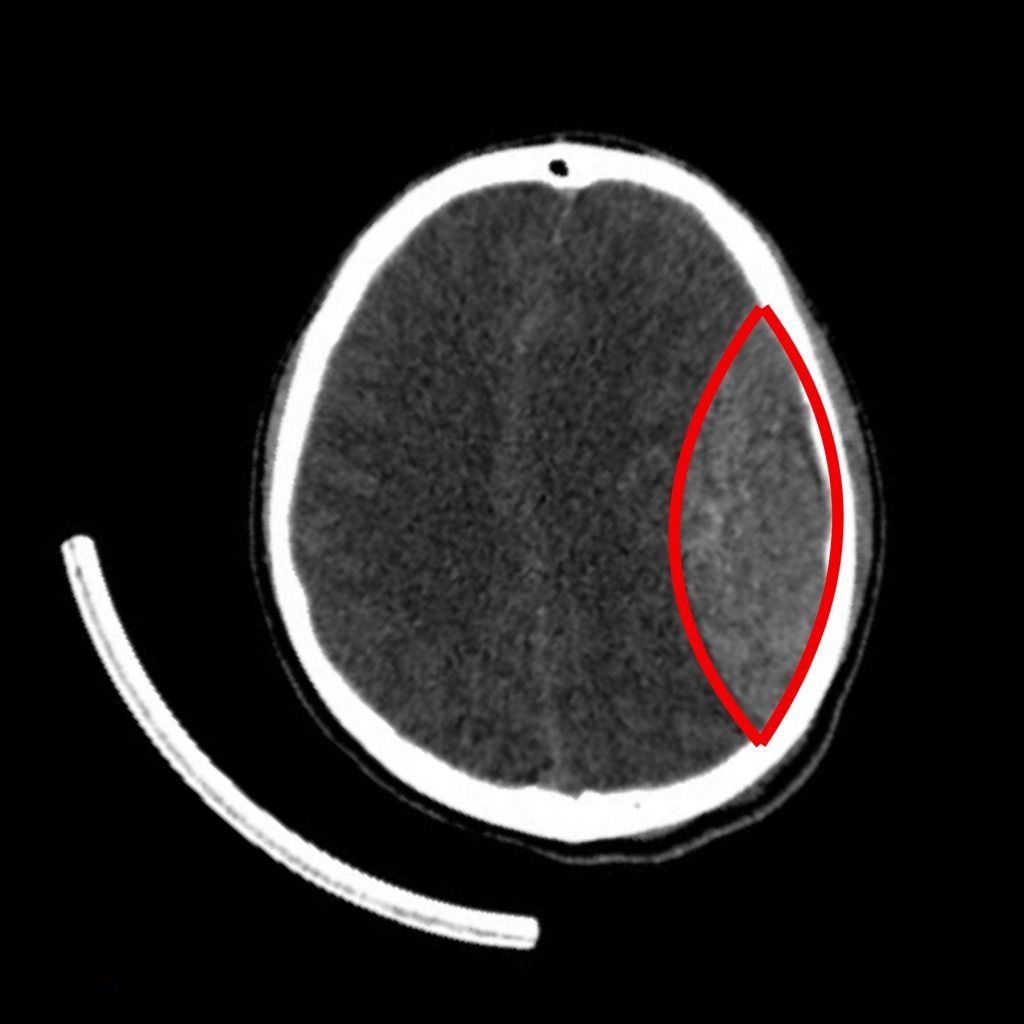

Kết quả chụp MSCT sọ não ghi nhận khối máu tụ ngoài màng cứng cấp tính vùng thái dương – đỉnh trái, kèm theo nứt xương sọ thái dương trái. Khối máu tụ lớn, ước tính khoảng 65 cc, gây chèn ép nhu mô não, khiến tri giác suy giảm nhanh.

Hình ảnh cận lâm sàng trước phẫu thuật